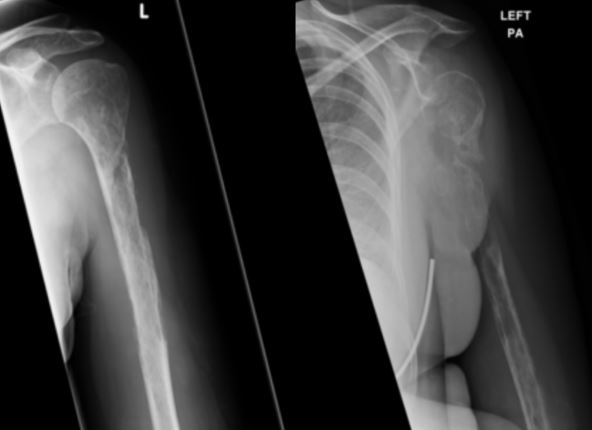

Žena stara 44 godine, čije ime nije objavljeno, imala je bolove u ruci i ramenu koji nikako nisu mogli da prođu. Rendgenski snimci urađeni u više navrata pokazali su čudnu pojavu - izgledalo je kao da njene kosti nestaju!

Na svakom sledećem snimku, kost ruke bila je sve bleđa i bleđa... Na kraju je utvrđeno da žena boluje od Goram-Stautovog sindroma, nazvanog u narodu i "bolest nestajućih kostiju". Izuzetno retka bolest zabeležena je svega u nekoliko desetina slučajeva u čitavom svetu!

Ovaj retki fenomen podrazumeva da se tkivo kostiju polako degeneriše, a da ga zamenjuju krvni i limfni sudovi koji rastu i prodiru u kost, i praktično je zamenjuju. Nisu poznati uzroci ove bizarne bolesti u kojoj benigni tumori krvnih sudova i vezivnog tkiva zamene koštano tkivo kao u naučno-fantastičnom filmu.